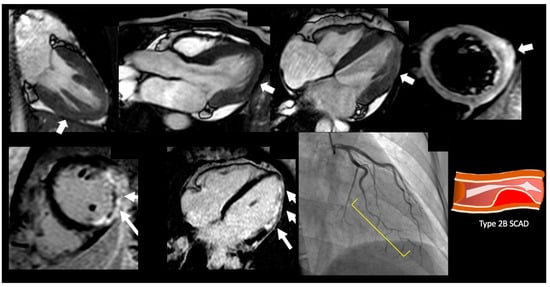

6. Acute MI

7. Stress-Induced Cardiomyopathy